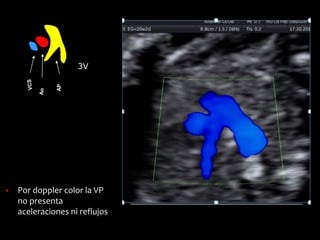

▪ Por doppler color la VP

no presenta

aceleraciones ni reflujos